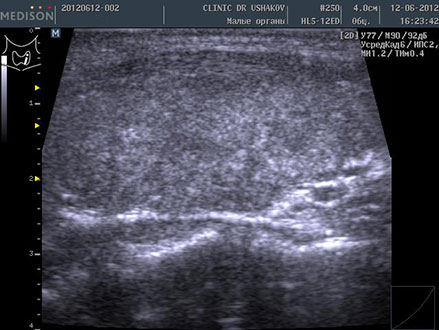

Пациентка К., 39 лет. При обследовании выявлены явления гипотиреоза и аутоиммунного тиреоидита. Через 1,5 года после лечебных мероприятий (в Клинике и соблюдение благоприятных условий) вместе с улучшением самочувствия произошло значительное восстановление щитовидной железы. В период лечения в связи с компенсированностью организма и гормонального обмена (Т4св. и Т3св.) и оздоровительным образом жизни медикаменты не применялись.

До лечения тиреоидита Анализ крови 9.06.2012 ТТГ 32 мЕд/л, Т4 св. 0,85 нг/дл АТ-ТПО 2113 ЕД/л | После лечения тиреоидита Анализ крови 15.01.2014 ТТГ 3,09 мЕд/л, Т4 св. 1,09 нг/дл АТ-ТПО 31,8 ЕД/л |

| В левой доле (в сосудистом режиме; ЦДК) заметно усиление кровотока ― свойственно избыточному напряжению железы | В левой доле (в сосудистом режиме; ЦДК) кровоток восстановился до оптимальной интенсивности ― нормальное состояние железы |